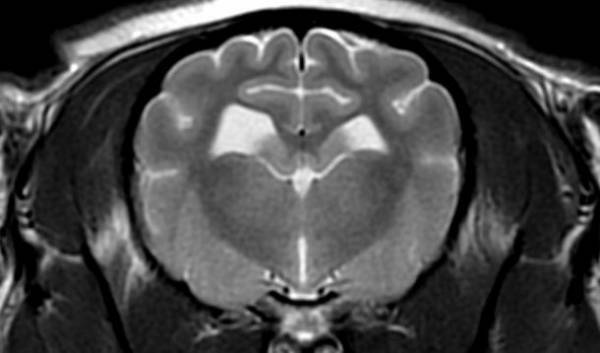

■MRI検査

強力な磁石と電波を用いて体内の水・脂肪成分の情報を収集し、断層像を得る検査です。軟部組織のコントラストが非常に優れているため、特に脳や脊髄といった中枢神経系の検査に威力を発揮します。

MRI検査画像

GE社製 1.5T MRI装置 SIGNA Explorer

■MRI検査

強力な磁石と電波を用いて体内の水・脂肪成分の情報を収集し、断層像を得る検査です。軟部組織のコントラストが非常に優れているため、特に脳や脊髄といった中枢神経系の検査に威力を発揮します。

MRI検査画像

GE社製 1.5T MRI装置 SIGNA Explorer